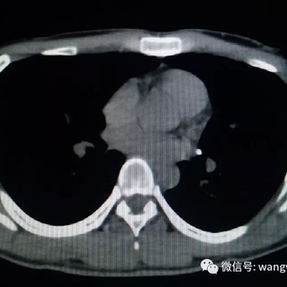

Preoperative Examination

The patient’s anterior chest wall exhibits a prominent depression deformity,characterized by a horizontal groove that affects both sides of the anterior chest wall. There is a surgical scar along the midline and one on the left side, with two scars visible on the right side of the chest wall. A 4x4 cm mass is located on the left chest wall, characterized by darkened skin and noticeable fluctuation upon palpation. The mass extends deep into the intercostal space. Mild scoliosis is also observed. The patient was ultimately diagnosed with grooved chest.

1. Inappropriate Surgical Procedure: grooved chest presents as a relatively flat, horizontal groove-like depression, which differs significantly from the bowl- or cup-shaped depression observed in pectus excavatum. Due to the insufficient height difference between the bottom and edges of the depression, grooved chest cannot provide adequate support points for the Nuss procedure, which is a necessary condition for flipping the bars to elevate the depression during the Nuss procedure, and is directly related to the success of the operation. Therefore, the inappropriate surgical approach is the main reason for the failure of the patient's initial surgery.

2. Improper bar Placement and Positioning: Preoperative imaging reveals that the bar was positioned along the upper edge of the groove-like depression and was placed at an angle.For optimal support and effective correction of the depressed bony structure, the bar should have been positioned at the base of the depression.